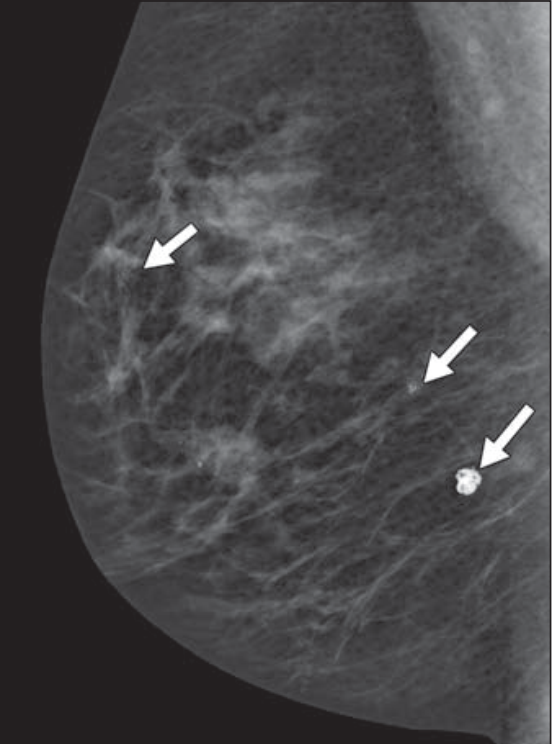

1.乳腺腺病分型1.1小葉增生型小葉增生型乳腺腺病主要表現(xiàn)為乳腺小葉的增生與肥大,其病理特征是乳腺腺泡和小導(dǎo)管的局灶性增生,并伴隨結(jié)締組織的增生,導(dǎo)致小葉結(jié)構(gòu)失去正常形態(tài)。這種類型的乳腺腺病在臨床上較為常見,多見于中年女性,尤其是40至50歲的年齡段。患者常表現(xiàn)為乳房疼痛,疼痛具有周期性特點(diǎn),即在月經(jīng)前明顯,月經(jīng)后減輕;乳房腫塊則可能表現(xiàn)為大小不一、邊界不清的結(jié)節(jié),有時可觸及多個腫塊。據(jù)研究,小葉增生型患者中月經(jīng)常不規(guī)則、經(jīng)期短、月經(jīng)量少的比例較高,約為30%-40%。影像學(xué)檢查中,鉬靶X線攝影顯示增生的乳腺密度增高呈結(jié)節(jié)狀或毛玻璃狀,病變形態(tài)不規(guī)則,邊緣一般模糊不清;B超檢查則顯示乳腺內(nèi)結(jié)構(gòu)紊亂,腺體組織回聲增粗,光點(diǎn)增強(qiáng)呈顆粒狀。1.2纖維腺病型纖維腺病型乳腺腺病的特點(diǎn)是乳腺腺體和纖維組織的混合性增生,形成邊界較清楚的腫塊,質(zhì)地中等。此類型乳腺腺病的腫塊一般較小,直徑多在2cm以上,形狀不一,呈片塊狀、結(jié)節(jié)狀和條索狀等,邊緣不甚清楚?;颊咛弁窗Y狀相對較輕,腫塊觸痛次之。在影像學(xué)表現(xiàn)上,鉬靶X線攝影可見病變局限于乳房的某一區(qū)域或廣泛彌散于乳房中,整個乳腺密度增高,正常的腺體結(jié)構(gòu)消失,病變陰影趨向融合。B超檢查中,增生結(jié)節(jié)表現(xiàn)為邊界不清的不均勻低回聲區(qū),或低回聲區(qū)帶狀強(qiáng)回聲交織形成的網(wǎng)狀陰影。1.3硬化性腺病型硬化性腺病型是乳腺腺病的一個特殊亞型,其病變特征為腺體和小管呈小葉中的顯著增生,伴有纖維組織的硬化,導(dǎo)致小葉結(jié)構(gòu)基本失去正常形態(tài),質(zhì)地較硬,有時易被誤診為癌。患者通常無明顯疼痛,腫塊觸痛不明顯。影像學(xué)檢查中,鉬靶X線攝影顯示硬化性腺病有局限性密度增高,邊緣模糊,呈非對稱性致密影表現(xiàn),形似浸潤性病變。此外,硬化性腺病可合并出現(xiàn)鈣化,鈣化最多見的是成簇分布的不定形點(diǎn)狀鈣化。B超檢查則顯示乳腺內(nèi)結(jié)構(gòu)紊亂,腺體組織回聲增粗,光點(diǎn)增強(qiáng)呈顆粒狀,增生結(jié)節(jié)表現(xiàn)為邊界不清的不均勻低回聲區(qū)。2.影像學(xué)表現(xiàn)2.1鉬靶X線攝影表現(xiàn)鉬靶X線攝影是乳腺疾病診斷中常用的影像學(xué)檢查方法之一,對于乳腺腺病的不同分型有以下表現(xiàn):?小葉增生型:鉬靶X線攝影顯示增生的乳腺密度增高呈結(jié)節(jié)狀或毛玻璃狀,病變形態(tài)不規(guī)則,邊緣一般模糊不清。彌漫性病變整個乳腺密度增高,正常的腺體結(jié)構(gòu)消失,病變陰影趨向融合。少數(shù)患者可有相對粗大的鈣化灶,廣泛地分布于病變區(qū)內(nèi)。?纖維腺病型:鉬靶X線攝影可見病變局限于乳房的某一區(qū)域或廣泛彌散于乳房中,整個乳腺密度增高,正常的腺體結(jié)構(gòu)消失,病變陰影趨向融合。?硬化性腺病型:鉬靶X線攝影顯示硬化性腺病有局限性密度增高,邊緣模糊,呈非對稱性致密影表現(xiàn),形似浸潤性病變。此外,硬化性腺病可合并出現(xiàn)鈣化,鈣化最多見的是成簇分布的不定形點(diǎn)狀鈣化。2.2B超檢查表現(xiàn)B超檢查在乳腺腺病的診斷中也具有重要價值,不同分型的乳腺腺病在B超檢查中的表現(xiàn)如下:?小葉增生型:B超檢查顯示乳腺內(nèi)結(jié)構(gòu)紊亂,腺體組織回聲增粗,光點(diǎn)增強(qiáng)呈顆粒狀。增生結(jié)節(jié)表現(xiàn)為邊界不清的不均勻低回聲區(qū),或低回聲區(qū)帶狀強(qiáng)回聲交織形成的網(wǎng)狀陰影,或類似“豹皮樣”回聲結(jié)構(gòu)。?纖維腺病型:B超檢查中,增生結(jié)節(jié)同樣表現(xiàn)為邊界不清的不均勻低回聲區(qū),或低回聲區(qū)帶狀強(qiáng)回聲交織形成的網(wǎng)狀陰影。由于纖維組織的增生,部分腫塊可能呈現(xiàn)一定的邊界,但內(nèi)部回聲依然不均勻。?硬化性腺病型:B超檢查顯示乳腺內(nèi)結(jié)構(gòu)紊亂,腺體組織回聲增粗,光點(diǎn)增強(qiáng)呈顆粒狀,增生結(jié)節(jié)表現(xiàn)為邊界不清的不均勻低回聲區(qū)。由于硬化性腺病的纖維組織增生較為明顯,腫塊的質(zhì)地較硬,在B超圖像上可能顯示出更明顯的低回聲區(qū)域,且內(nèi)部回聲更加不均勻。3.治療方法3.1一般治療一般治療是乳腺腺病治療的基礎(chǔ),主要包括以下幾個方面:?生活方式調(diào)整:患者應(yīng)保持規(guī)律的作息時間,每晚保證充足的睡眠,有助于維持身體的正常代謝和內(nèi)分泌平衡。減少攝入油膩、辛辣、刺激性食物,增加新鮮蔬菜、水果和優(yōu)質(zhì)蛋白的攝取。適度的體育鍛煉,如慢跑、瑜伽等,能夠增強(qiáng)體質(zhì),促進(jìn)血液循環(huán)。?情緒管理:長期的精神壓力、焦慮、抑郁等不良情緒可能加重病情,患者應(yīng)學(xué)會自我心理調(diào)適,保持積極樂觀的心態(tài)??梢酝ㄟ^參加社交活動、培養(yǎng)興趣愛好等方式,轉(zhuǎn)移注意力,舒緩情緒。必要時可尋求心理咨詢師的幫助,進(jìn)行專業(yè)的心理疏導(dǎo)。?穿著適宜的內(nèi)衣:避免穿戴過緊或不適的內(nèi)衣,以減少對乳房的壓迫,選擇合適的內(nèi)衣對于緩解癥狀和預(yù)防病情加重有積極作用。3.2藥物治療藥物治療是乳腺腺病的常用治療方法之一,主要包括以下幾類藥物:?維生素類藥物:?維生素A:可促進(jìn)無活性的過氧雄稀酮及孕稀酮轉(zhuǎn)變成有活性的雄稀酮和孕酮,后兩者有拮抗雌激素作用。常用量為每次2萬~5萬U,3次/d,口服。每次月經(jīng)結(jié)束后連用2周。但大劑量久服,可引起食欲不振、腹瀉、四肢疼痛、肝臟增大、嗜睡、嘔吐等不良反應(yīng)。?維生素E:是一種抗氧化劑,可抑制細(xì)胞間變,調(diào)節(jié)卵巢功能使血清黃體酮/雌二醇比值上升,使成熟卵泡增多,黃體細(xì)胞增大,并抑制孕酮氧化,增加了孕酮的作用,從而糾正內(nèi)分泌紊亂。常用量為每次100mg,3次/d,口服,連用3個月。?維生素B6:主要參與蛋白質(zhì)及氨基酸的代謝。維生素B6缺乏者可引起經(jīng)前緊張,雌激素過剩。本藥對調(diào)節(jié)性激素平衡有一定作用。每次20mg,3次/d,口服。?激素治療:?雄激素療法:?甲睪酮(甲基睪丸素):每次5mg,2~3次/d,口服。每月總劑量不應(yīng)超過300mg。長期應(yīng)用可引起女性患者男性化等不良反應(yīng)。?丙酸睪酮:每天25mg,肌內(nèi)注射,共3~4天。如超量或長期應(yīng)用,也可引起與甲睪酮相同的不良反應(yīng)。?他莫昔芬(三苯氧胺):對癥狀較重的患者,采用持續(xù)給藥,每次10mg,2次/d,口服。對一般患者采用周期性給藥,在月經(jīng)后2~5天開始口服他莫昔芬,共用藥15~20天。停藥后有一定的復(fù)發(fā)率。服藥時間較長的病人,停藥后復(fù)發(fā)率減少,復(fù)發(fā)時間也較晚。?溴隱亭:?連續(xù)性給藥:即從月經(jīng)來潮后第5天開始給藥,到月經(jīng)來潮時停止,連續(xù)停藥4天。從小劑量開始;第1周前3天1次服1.25mg,2次/d,后4天改為3次/d;第2周前3天,1次用2.5mg,2次/d,后4天均為3次/d,每次服2.5mg;以后一直維持此劑量不變。?周期性給藥:即月經(jīng)來潮后的第11~13天,每天用藥1.25mg;第14天至下次月經(jīng)來潮時服用1.25mg,2次/d。用藥時間不超過6個月。?中藥治療:?全身治療:采用疏肝理氣、化瘀散結(jié)的方法??捎弥谐伤幦轳毕⑷榧矊幤?、乳康片、乳結(jié)消顆粒等藥內(nèi)服。具體劑量為柴胡9g、制香附9g、當(dāng)歸12g、赤白芍(各)12g、青陳皮(各)6g、全瓜蔞15g、桃仁12g、生牡蠣30g、澤蘭12g、生甘草3g。若腫塊痛甚者加炙乳沒藥(各)4.5g、延胡9g、腫塊質(zhì)堅(jiān)加三棱9g、莪術(shù)12g、海藻12g、月經(jīng)量少加益母草5g、丹參12g、月經(jīng)提前加黃精12g、女貞子12g。煎服。?局部治療:還可選用乳結(jié)消貼膏及藥物胸罩外用。特別是乳塊消貼膏對乳癖(乳腺囊生增生?。┚哂辛己玫闹委熥饔茫R床上取得較好療效。該藥能減輕或消除乳房腫塊,緩解或消除乳房腫塊疼痛,改善臨床癥狀,尤其是對乳房腫塊疼痛減輕的起效時間快,對心、肝、腎、及造血系統(tǒng)近期之內(nèi)無明顯損害,使用安全。3.3手術(shù)治療手術(shù)治療適用于乳腺腺病病情較為嚴(yán)重,如腫塊較大、質(zhì)地堅(jiān)硬、藥物治療無效或懷疑有惡變傾向的情況。手術(shù)方式主要包括:?腫塊局部切除術(shù):針對病變較局限的腫塊進(jìn)行切除,手術(shù)創(chuàng)傷相對較小,能夠有效去除病灶,緩解癥狀。在手術(shù)過程中,應(yīng)仔細(xì)觀察腫塊的形態(tài)、質(zhì)地和邊界,確保完整切除病變組織。同時,術(shù)中應(yīng)做冰凍切片,以明確診斷,避免誤診而行不應(yīng)做的乳腺癌根治術(shù)。?乳腺區(qū)段切除術(shù):當(dāng)病變范圍較廣,累及乳腺的某一區(qū)域時,可選擇乳腺區(qū)段切除術(shù)。這種手術(shù)方式可以更廣泛地切除病變組織,減少復(fù)發(fā)的可能性。手術(shù)時需注意保護(hù)乳腺的正常組織和結(jié)構(gòu),盡量保持乳房的外形美觀。?經(jīng)皮下乳腺全切術(shù):對于腫塊較多,且藥物治療效果不佳的患者,可考慮行經(jīng)皮下乳腺全切術(shù)。此手術(shù)方式可以徹底切除乳腺組織,有效解決病情,但會對乳房外觀產(chǎn)生較大影響。因此,在選擇此手術(shù)方式時,需充分考慮患者的心理承受能力和對外觀的要求。4.總結(jié)乳腺腺病是一種常見的乳腺良性疾病,其分型、影像學(xué)表現(xiàn)和治療方法具有各自的特點(diǎn)和重要性。通過以上研究,我們可以得出以下結(jié)論:4.1分型特點(diǎn)?小葉增生型:以乳腺小葉的增生與肥大為主,多見于中年女性,臨床表現(xiàn)為周期性乳房疼痛和大小不一的腫塊,影像學(xué)檢查顯示乳腺密度增高、結(jié)構(gòu)紊亂。?纖維腺病型:乳腺腺體和纖維組織混合性增生形成邊界較清楚的腫塊,質(zhì)地中等,疼痛癥狀較輕,影像學(xué)上病變局限于乳房的某一區(qū)域或廣泛彌散,密度增高,腺體結(jié)構(gòu)消失。?硬化性腺病型:腺體和小管顯著增生伴有纖維組織硬化,質(zhì)地較硬,易誤診為癌,患者通常無明顯疼痛,影像學(xué)檢查顯示局限性密度增高、邊緣模糊,可合并鈣化。4.2影像學(xué)表現(xiàn)的重要性影像學(xué)檢查在乳腺腺病的診斷中發(fā)揮著關(guān)鍵作用。鉬靶X線攝影能夠顯示乳腺密度的增高、病變的形態(tài)和分布以及鈣化情況,有助于區(qū)分不同分型的乳腺腺病。B超檢查則可以清晰地觀察到乳腺內(nèi)結(jié)構(gòu)的紊亂、腺體組織的回聲變化以及增生結(jié)節(jié)的邊界和內(nèi)部回聲,為臨床診斷提供了重要的參考依據(jù)。這些影像學(xué)表現(xiàn)不僅有助于醫(yī)生對乳腺腺病進(jìn)行準(zhǔn)確分型,還能與其他乳腺疾病進(jìn)行鑒別診斷,如與乳腺癌的區(qū)分,從而避免誤診和過度治療。4.3治療方法的多樣性與選擇乳腺腺病的治療方法多樣,包括一般治療、藥物治療和手術(shù)治療。一般治療是基礎(chǔ),通過生活方式調(diào)整、情緒管理和穿著適宜的內(nèi)衣等措施,可以改善患者的整體健康狀況,緩解癥狀。藥物治療是常用手段,維生素類藥物、激素治療和中藥治療等各有其作用機(jī)制和適應(yīng)癥,能夠針對不同的癥狀和病理變化進(jìn)行調(diào)節(jié)和治療。手術(shù)治療適用于病情較為嚴(yán)重的情況,如腫塊較大、質(zhì)地堅(jiān)硬、藥物治療無效或懷疑有惡變傾向等,通過腫塊局部切除術(shù)、乳腺區(qū)段切除術(shù)或經(jīng)皮下乳腺全切術(shù)等方式,可以有效去除病灶,但需注意手術(shù)風(fēng)險和對乳房外觀的影響。在臨床實(shí)踐中,醫(yī)生應(yīng)根據(jù)患者的具體病情、分型特點(diǎn)和影像學(xué)表現(xiàn),綜合考慮各種治療方法的優(yōu)勢和局限性,制定個體化的治療方案,以達(dá)到最佳的治療效果。

乳腺鈣化灶需要根據(jù)鈣化灶的具體形態(tài)決定是否需要手術(shù)治療。乳腺鈣化灶的發(fā)現(xiàn)主要依賴于鉬靶檢查。鉬靶影像學(xué)顯示的乳腺鈣化灶種類,包括典型良性鈣化、中間性鈣化以及高度惡性鈣化。典型良性鈣化:如爆米花樣鈣化、圓形中空鈣化、環(huán)形鈣化等,良性鈣化一般無需手術(shù)治療。中間性鈣化:包括不定形模糊鈣化及粗糙不均質(zhì)鈣化兩型,不定形模糊鈣化一般為良性,鈣化灶較小,典型特征不明顯。粗糙不均質(zhì)鈣化惡性和良性均有可能,其鈣化灶形態(tài)不規(guī)則,判斷良惡性一般需要結(jié)合臨床,若為良性,則不需要手術(shù),若為惡性,則需要進(jìn)行手術(shù)。高度惡性鈣化:常見多形性不均質(zhì)鈣化,大小形態(tài)不一,可呈簇狀、針尖樣、細(xì)鹽粒樣表現(xiàn),多為不連續(xù)的鈣化灶,通常需要通過手術(shù)切除、影像科專業(yè)醫(yī)生對于鉬靶片的解讀根據(jù)上述情況綜合分析,如果鉬靶評估為BI-RADS3類以下,多需要每6-12個月復(fù)查。如果評估為為BI-RADS4類以上,往往需要行病理學(xué)診斷。尤其對于乳腺鈣化灶BI-RADS4B類以上的病例,則不排除存在惡性可能,需要盡早進(jìn)一步檢查及明確病理診斷。乳腺鈣化灶的手術(shù)方式包括導(dǎo)絲定位手術(shù)切除術(shù)和現(xiàn)階段先進(jìn)的鈣化灶三維立體定位微創(chuàng)旋切術(shù)。筆者開展鈣化灶三維立體定位微創(chuàng)旋切術(shù)多年,對于范圍較小,較為集中的鈣化灶可以起到切除病變,明確病理性質(zhì)和美容微創(chuàng)的雙重效果。

乳腺鈣化灶發(fā)生的原因很多,應(yīng)區(qū)別對待處理。乳腺鈣化灶是指乳腺組織內(nèi)出現(xiàn)的鈣沉積現(xiàn)象,其形成原因較多,主要的原因有導(dǎo)管內(nèi)癌壞死、良性腫瘤鈣化、腫瘤分泌出的鈣鹽沉積、血管鈣化、乳腺導(dǎo)管內(nèi)沉積物年久鈣化等。乳腺鈣化灶常常是患者進(jìn)行乳腺鉬靶攝片時,顯示乳房內(nèi)有鈣質(zhì)沉積。如果鈣化灶較大,乳腺彩超檢查也有能發(fā)現(xiàn)。鉬靶攝片是鈣化灶的首選檢查,如果鈣化灶較粗大或散在往往是良性表現(xiàn)。如果鈣化灶越細(xì)小密集,醫(yī)學(xué)表述為細(xì)鹽粒樣或針尖樣鈣化,則需要高度關(guān)注。臨床上通常將直徑小于1mm的鈣化歸為微鈣化,早期乳腺癌比如導(dǎo)管內(nèi)癌的主要特征是乳腺微鈣化灶,在乳腺癌早期時發(fā)現(xiàn)乳腺微鈣化灶則提示可能為乳腺癌。需要注意的是并不是所有的乳腺癌都出現(xiàn)微鈣化現(xiàn)象,臨床上通常通過觀察鈣化的分布和形態(tài)來鑒別乳腺微鈣化灶的良惡性。如果臨床考慮惡性鈣化可能,這時往往需要采取鉬靶導(dǎo)絲定位區(qū)段切除術(shù),如果鈣化灶范圍較小,也可以采取鉬靶三維立體定位微創(chuàng)旋切術(shù)切除病變,明確病理性質(zhì)。如果切除物病理提示確為乳腺癌,則需要進(jìn)一步行全麻下乳腺癌手術(shù)。如果臨床考慮乳腺鈣化灶為良性,通常不用過于擔(dān)心,需要每半年復(fù)查彩超,酌情每一年左右定期復(fù)查鉬靶即可。